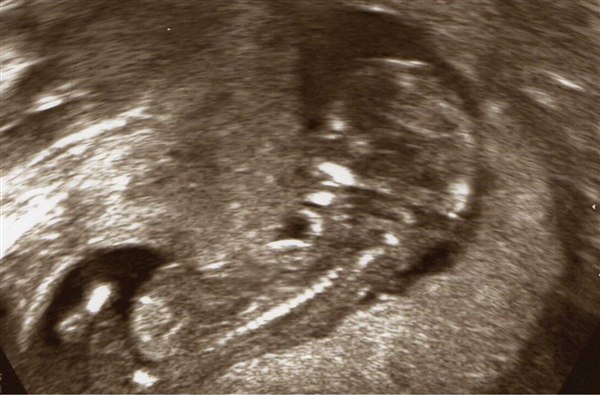

Så er dagen kommet hvor vi skal til kønsscanning og se om lille-niv er en lille pige eller lille dreng

Nu har der været nogle gæt omkring kønnet, og så tænkte jeg at jeg da kunne lave en lille gætte leg ud af det - så derfor har jeg sat billeder ind af lille-niv fra NF scanning og af min mave idag.

Vedhæftede fotos (klik for at se i fuld størrelse)